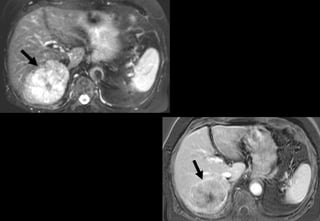

CT / IRM

CT/ IRM

Phát hiện CHC

• Kỹ thuật

– Ko cản quang T1 et T2

– Pha và đối pha+ diffusion

– Hình ảnh 2D hay 3D sau Gadolinum thì động

mạch, cửa và muộn

Quan trọng của thì tiêm thuốc